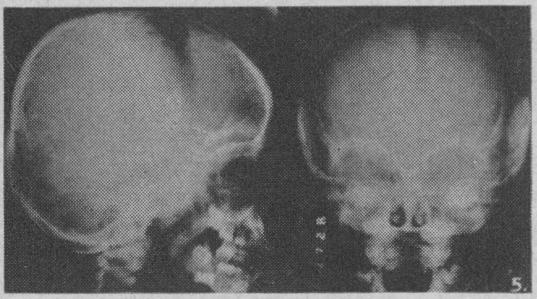

Adrenal neuroblastoma.

Can Med Assoc J. 1950 Aug;63(2):153-7.